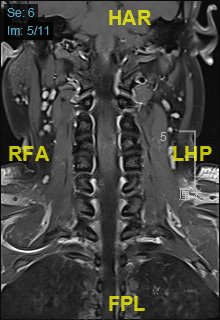

颈部磁共振平扫:

颈部磁共振平扫后增强: